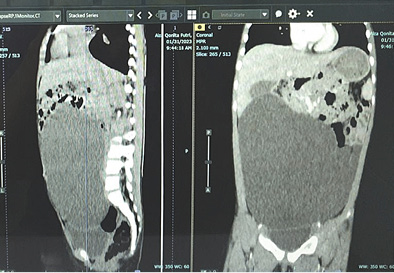

A 4-year-old girl reported having a abdominal distension for two months, there was no history of abdominal pain, vomiting, fever, and no disorders of respiratory or urinary system. Her growth and development were normal and no family history of similar illness; the anamnesis provided the diagnosis. Abdomen was distended with a 15 cm by 15 cm mass with dull percussion, non-tender smooth surface, well-defined border, movab­le from side to side in the top border, initially around the pelvic area and later to periumbilical area 1 cm under umbilical (Figure 1). Her blood profile, coagulation profile, albumin level, electrolytes, renal and liver functions tests were normal and no hepatitis B surface antigen was found. CT abdomen with intravenous contrast revealed a large cystic mass lesion (Figure 2) with internal septations, origin from the ovary with extending from the pelvis to the cavum abdomen. Other abdominal organs were normal.

Figure 2. Computed tomography of the abdomen demonstrated a AP 7.10 x LL 15.64 xx CC 14.97 cm cystic mass

Omental cysts are rare intra-abdominal tumors in children, which are reported incidence of one in twenty thousand admissions to a children’s hospital and female predominance by a factor of 1.5. Different etiological factors have been reported for development of these masses including a benign proliferation of mesenteric lymphatics, failed fusion of the mesenteric leaves, and deficiency of the lymphatico-venous shunts. The literature contains several of cysts which are definitely congenital, but there are also acquired cysts which have been reported. A female factor were found in our case. Presentation is often with abdominal pain with distention and/or palpable abdominal mass, a very small cyst may be asymptomatic and nonpalpable. Disorders of the respiratory or urinary system, in addition to symptoms caused by compression of the portal vein, are often seen because of cyst enlargement. In our case we found a abdominal distension with palpable mass for two months with no history of abdominal pain, and no disorders of respiratory or urinary system. These cysts are usually diagnosed incidentally by abdominal imaging or discovered as an incidental finding at operation. Since it is a rare condition and there are lack of specific symptoms, a correct pre-operative diagnosis is difficult. Our patient underwent CT scanning, allowing us to locate the cyst precisely and identify its relation to the surrounding tissues, leading to a diagnosis of ovarian cyst at first. In laparotomy, we found a giant omental cyst, not originating from the ovaries, and did an omentectomy to excision the cyst. CT scan shows that the giant abdominal cyst is difficult to identify between omental, mesenteric, and ovarian cysts. Precise identification of stomach cysts is necessary. Also, doctors need to read the CT scan image more carefully.